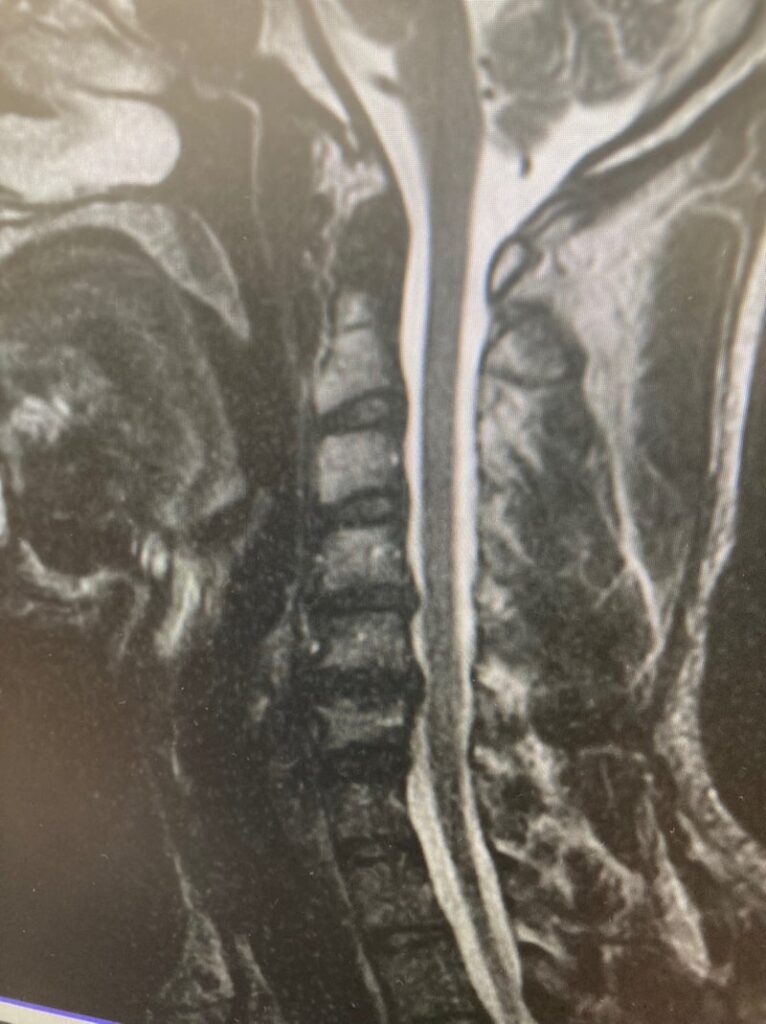

その結果、頚椎をはじめ、全身の複数箇所に深刻な怪我を抱え、引退を決断せざるを得ない結果となってしまいました。

引退のきっかけとなった頸椎の怪我に関しても

はじめは、「左腕の軽い違和感」から始まっています。

私の場合であれば、頚椎のダメージが深刻になる以前に

「左腕の強い痛み」「肩甲骨内側の筋肉の張り」「頭痛や首の痛み、全身の倦怠感」といった

身体からの様々な危険信号が多く表れていました。

当時を振り返れば、この段階で正しい対処を行う必要がありました。